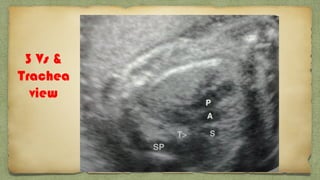

3 Vs &

Trachea

view